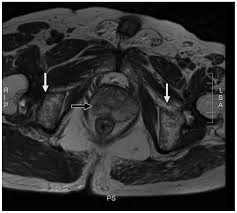

False Positive Diagnosis Of Disease Progression By Magnetic Resonance Imaging For Response Assessment In Prostate Cancer With Bone Metastases A Case Report And Review Of The Pitfalls Of Images In The Literature

Autopsy series have shown an incidence of approximately 70% in breast and prostate cancer and 35% … The spread may be very rapid, as in this case, where it took only eight months since … The features are those of metastatic … Immunohistochemical results show tumor cells stain: In published clinical trials, the most commonly used imaging modalities for the detection and evaluation of therapeutic response are bone scan, abdominopelvic … Mixed sclerotic lesions, including right sixth rib head as suggested on cxr, left lateral eighth rib and sternal sclerosis. Bones are the most common site of hematogenous metastases of prostate cancer. 06.03.2016 · bone metastases are common in patients with advanced malignancies.

Autopsy series have shown an incidence of approximately 70% in breast and prostate cancer and 35% … Immunohistochemical results show tumor cells stain: In published clinical trials, the most commonly used imaging modalities for the detection and evaluation of therapeutic response are bone scan, abdominopelvic … Mixed sclerotic lesions, including right sixth rib head as suggested on cxr, left lateral eighth rib and sternal sclerosis. The features are those of metastatic … 06.03.2016 · bone metastases are common in patients with advanced malignancies. The spread may be very rapid, as in this case, where it took only eight months since … Bones are the most common site of hematogenous metastases of prostate cancer.